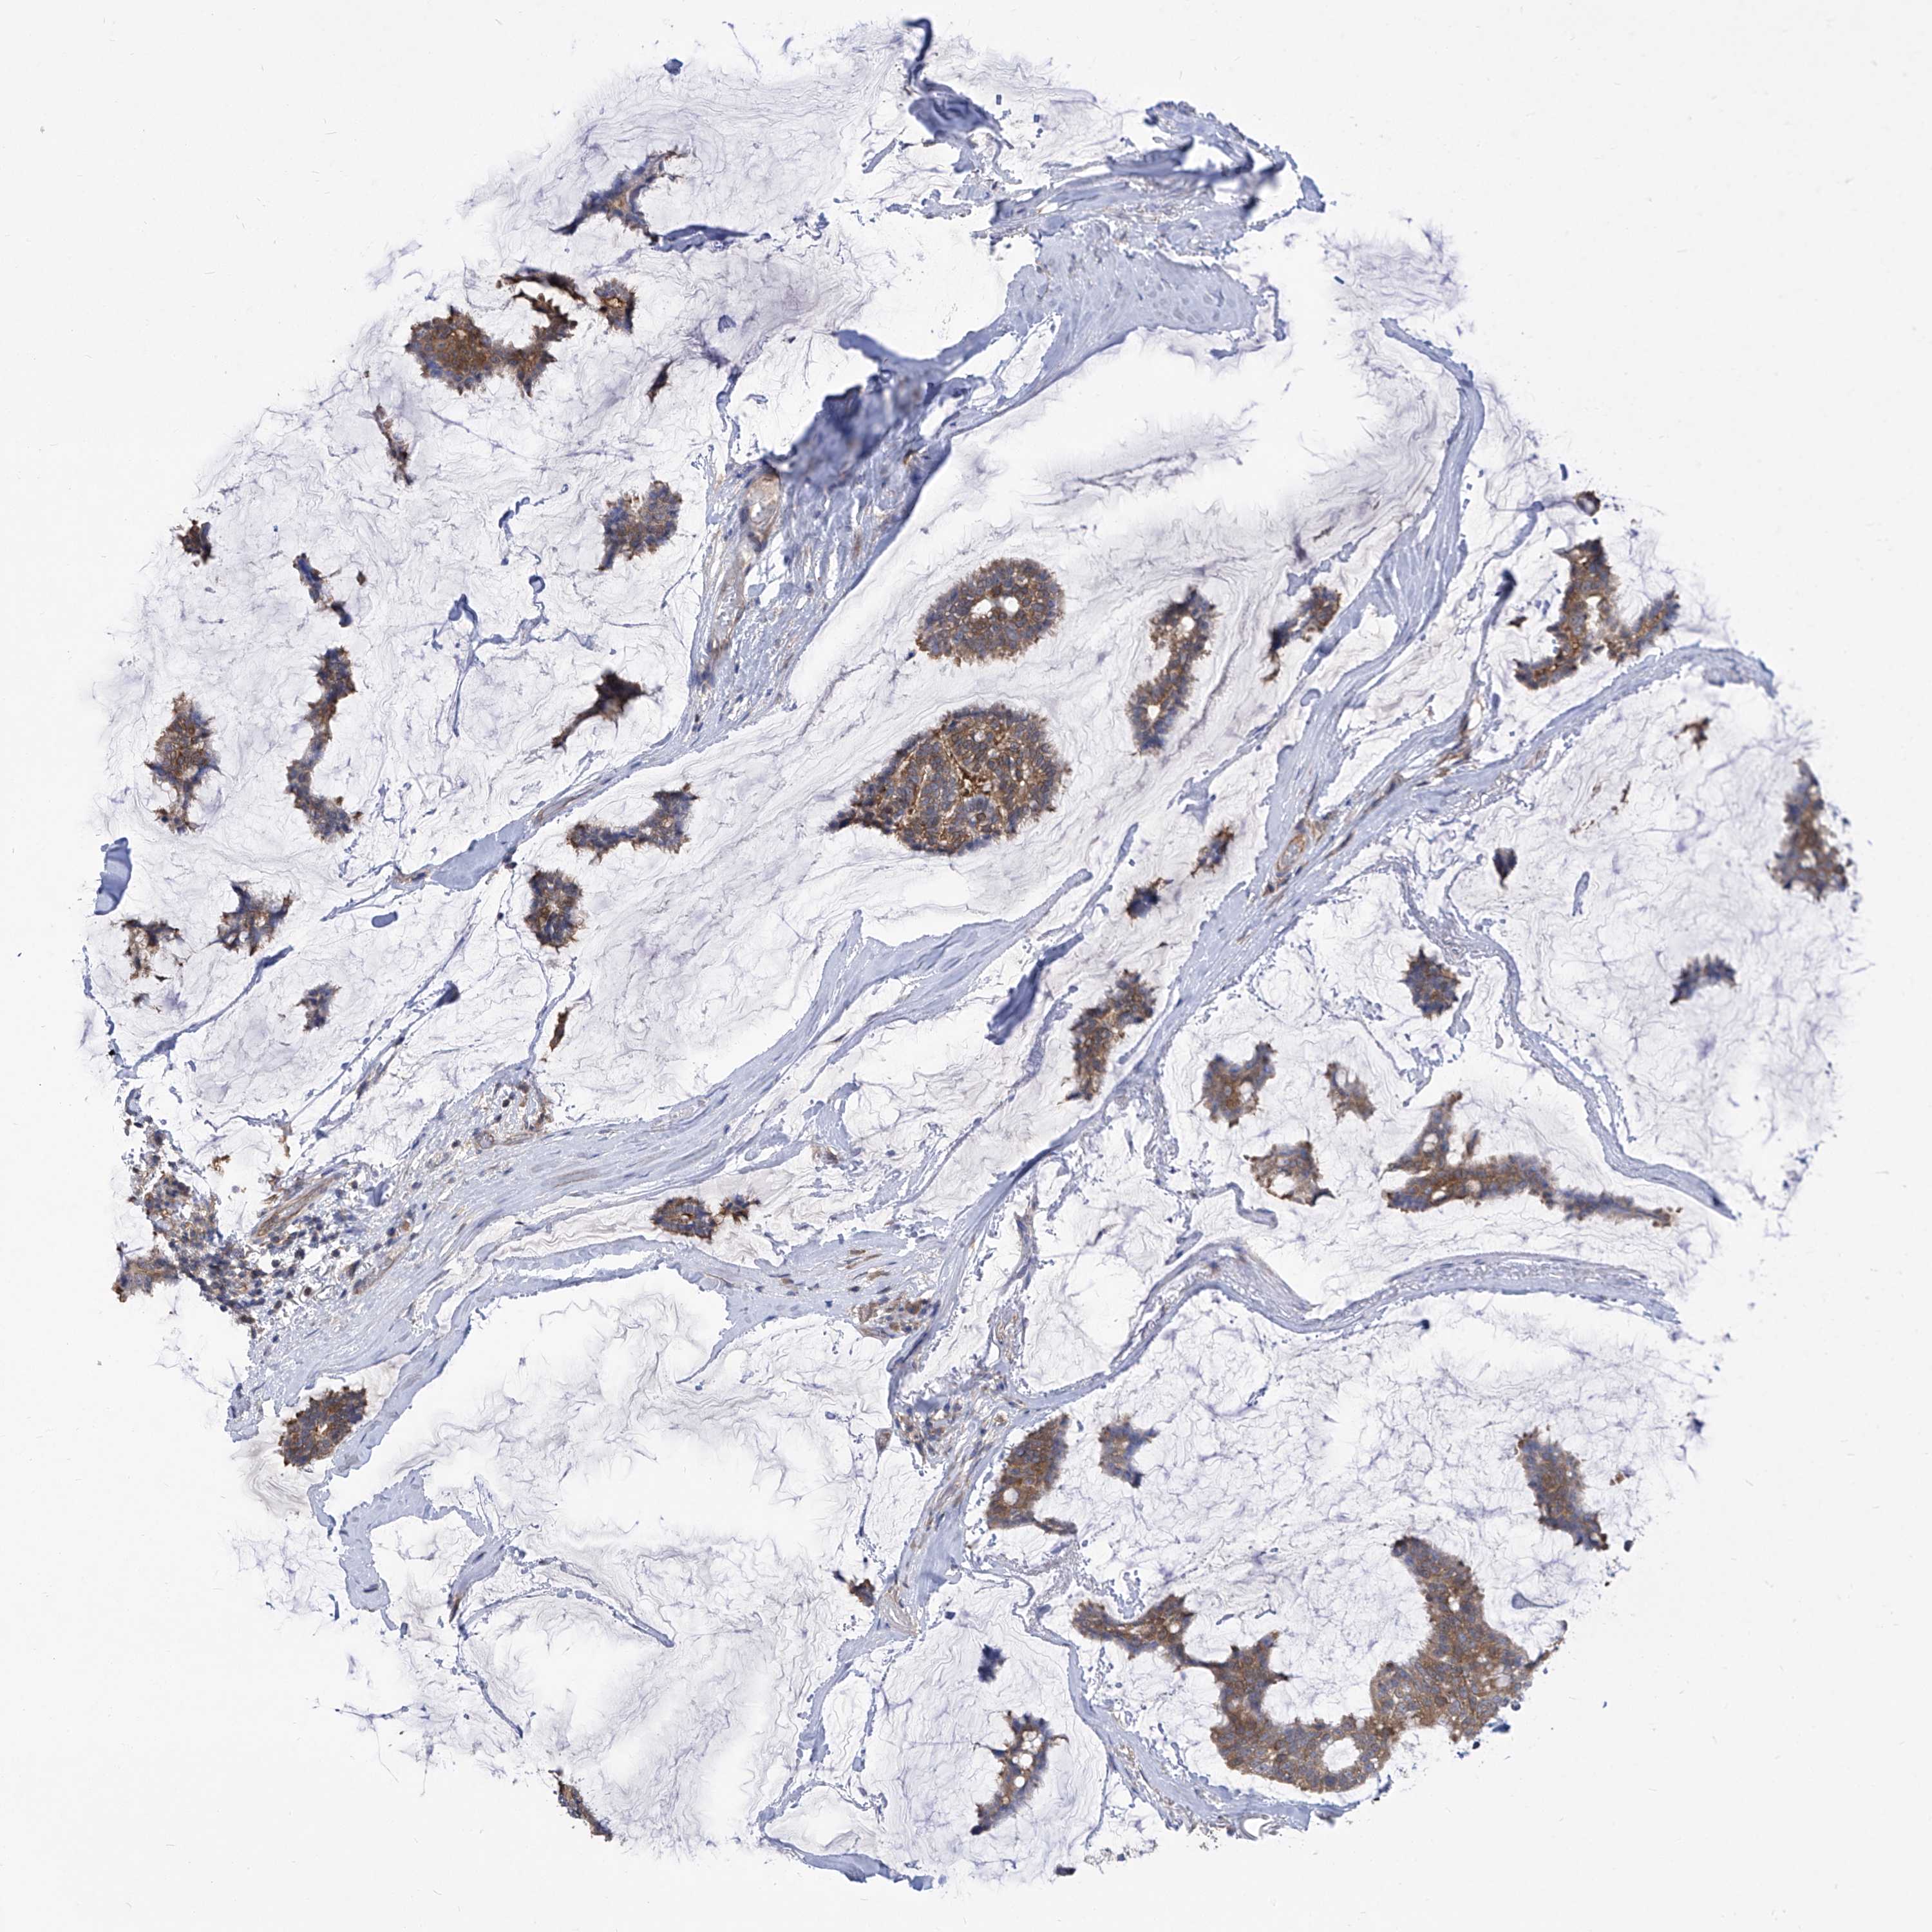

BRCA TCGA BRCA VALIDATION PROTEIN EXPRESSION